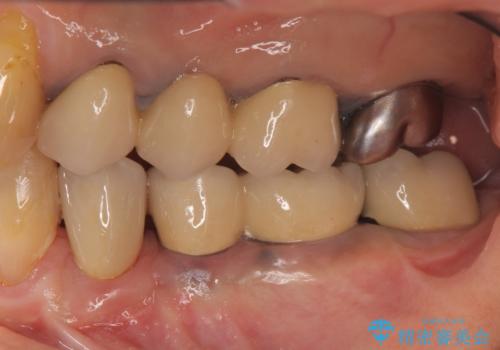

- 以前治療したブリッジが噛むと痛く、食事ができないことの改善を希望され来院されました。

X線写真より、過度な咬合支持負担により支台となる歯の周囲の骨吸収が認められます。今後安定してしっかりとかめるような環境を整備するためにインプラント治療を選択しました。

ブリッジ治療は支台となる歯が弱いと、今回のように周囲の骨が吸収したり歯が割れてしまったりといったトラブルがおきます。咬合力に対抗するため、今回はインプラントを用いて機能回復を行いました。